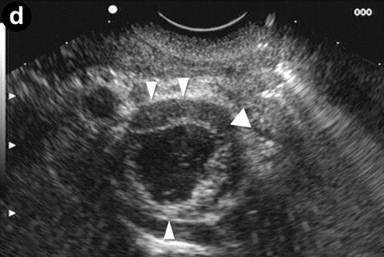

A 24-year-old man presenting with jaundice and elevated levels of IgG4 (366 mg/dL; reference range: 8-140 mg/dL). Magnetic resonance cholangiopancreatography (MRCP) was requested; the T2-weighted coronal scan (Image 1a) showed dilated intra- and extra-hepatic bile ducts with an abrupt stricture (arrow) of the intrapancreatic common bile duct; the pancreatic duct was narrowed throughout its course. Subsequent EUS (Image 1bc) revealed a diffusely and substantially enlarged pancreatic gland (arrowheads) with echopoor echotexture and a normal main pancreatic duct having a diameter of 1.3 mm (Image 1b, arrow), measured with calipers (Image 1c, arrow). Hyperechoic septa were well visible in the enlarged gland. Stenosis of the distal bile duct was due to a diffuse thickening of the wall with an intermediate echopoor layer, and echorich outer and inner layers ("sandwich-pattern") (Image 1d, arrowheads).